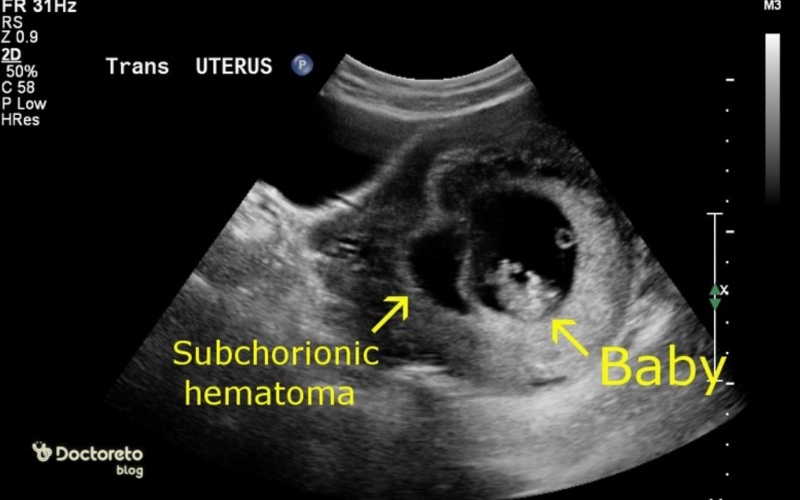

در بیشتر موارد، زمانی که از هماتوم بارداری صحبت میشود منظور هماتوم سابکوریونیک، یکی از انواع هماتوم در بارداری است؛ این نوع هماتوم ناحیهای از خونریزی است که بین پوشش بارداری (کوریون) و دیواره رحم یا پشت جفت جمع شده است. این وضعیت بیشتر در سهماهه اول دیده میشود و یک یافته سونوگرافی است.

عکس هماتوم در بارداری

موارد بالا، عکس هماتوم در بارداری را نشان میدهند. گاهی بخشی از خون جمعشده بهصورت لختههای تیره یا ترشحات قهوهای از واژن خارج میشود. در عکس هماتوم دفعشده، معمولا لختهها شبیه تودههای ژلاتینی یا خون خشکشده دیده میشوند.

تشخیص هماتوم بارداری معمولا بر پایه سونوگرافی است. در سونوگرافی واژینال یا شکمی، رادیولوژیست ناحیهای تیرهتر یا متفاوت در اطراف کیسه بارداری یا پشت جفت را میبیند که با وجود هماتوم در بارداری سازگار است. گاهی این یافته در خانمی کشف میشود که با لکهبینی مراجعه کرده و گاهی در یک سونوگرافی روتین بدون هیچ علامتی دیده میشود. برای پیگیری، معمولا سونوهای دورهای انجام میشود تا مشخص شود هماتوم در دوران بارداری کوچک شده، ثابت مانده یا بزرگتر شده است.